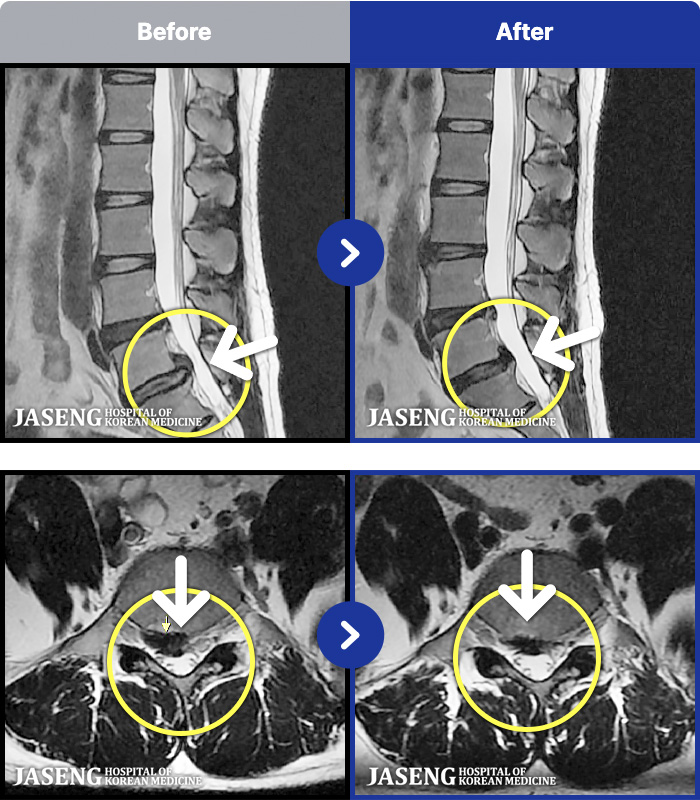

54 MRI ũ ʸ Ȯϼ.